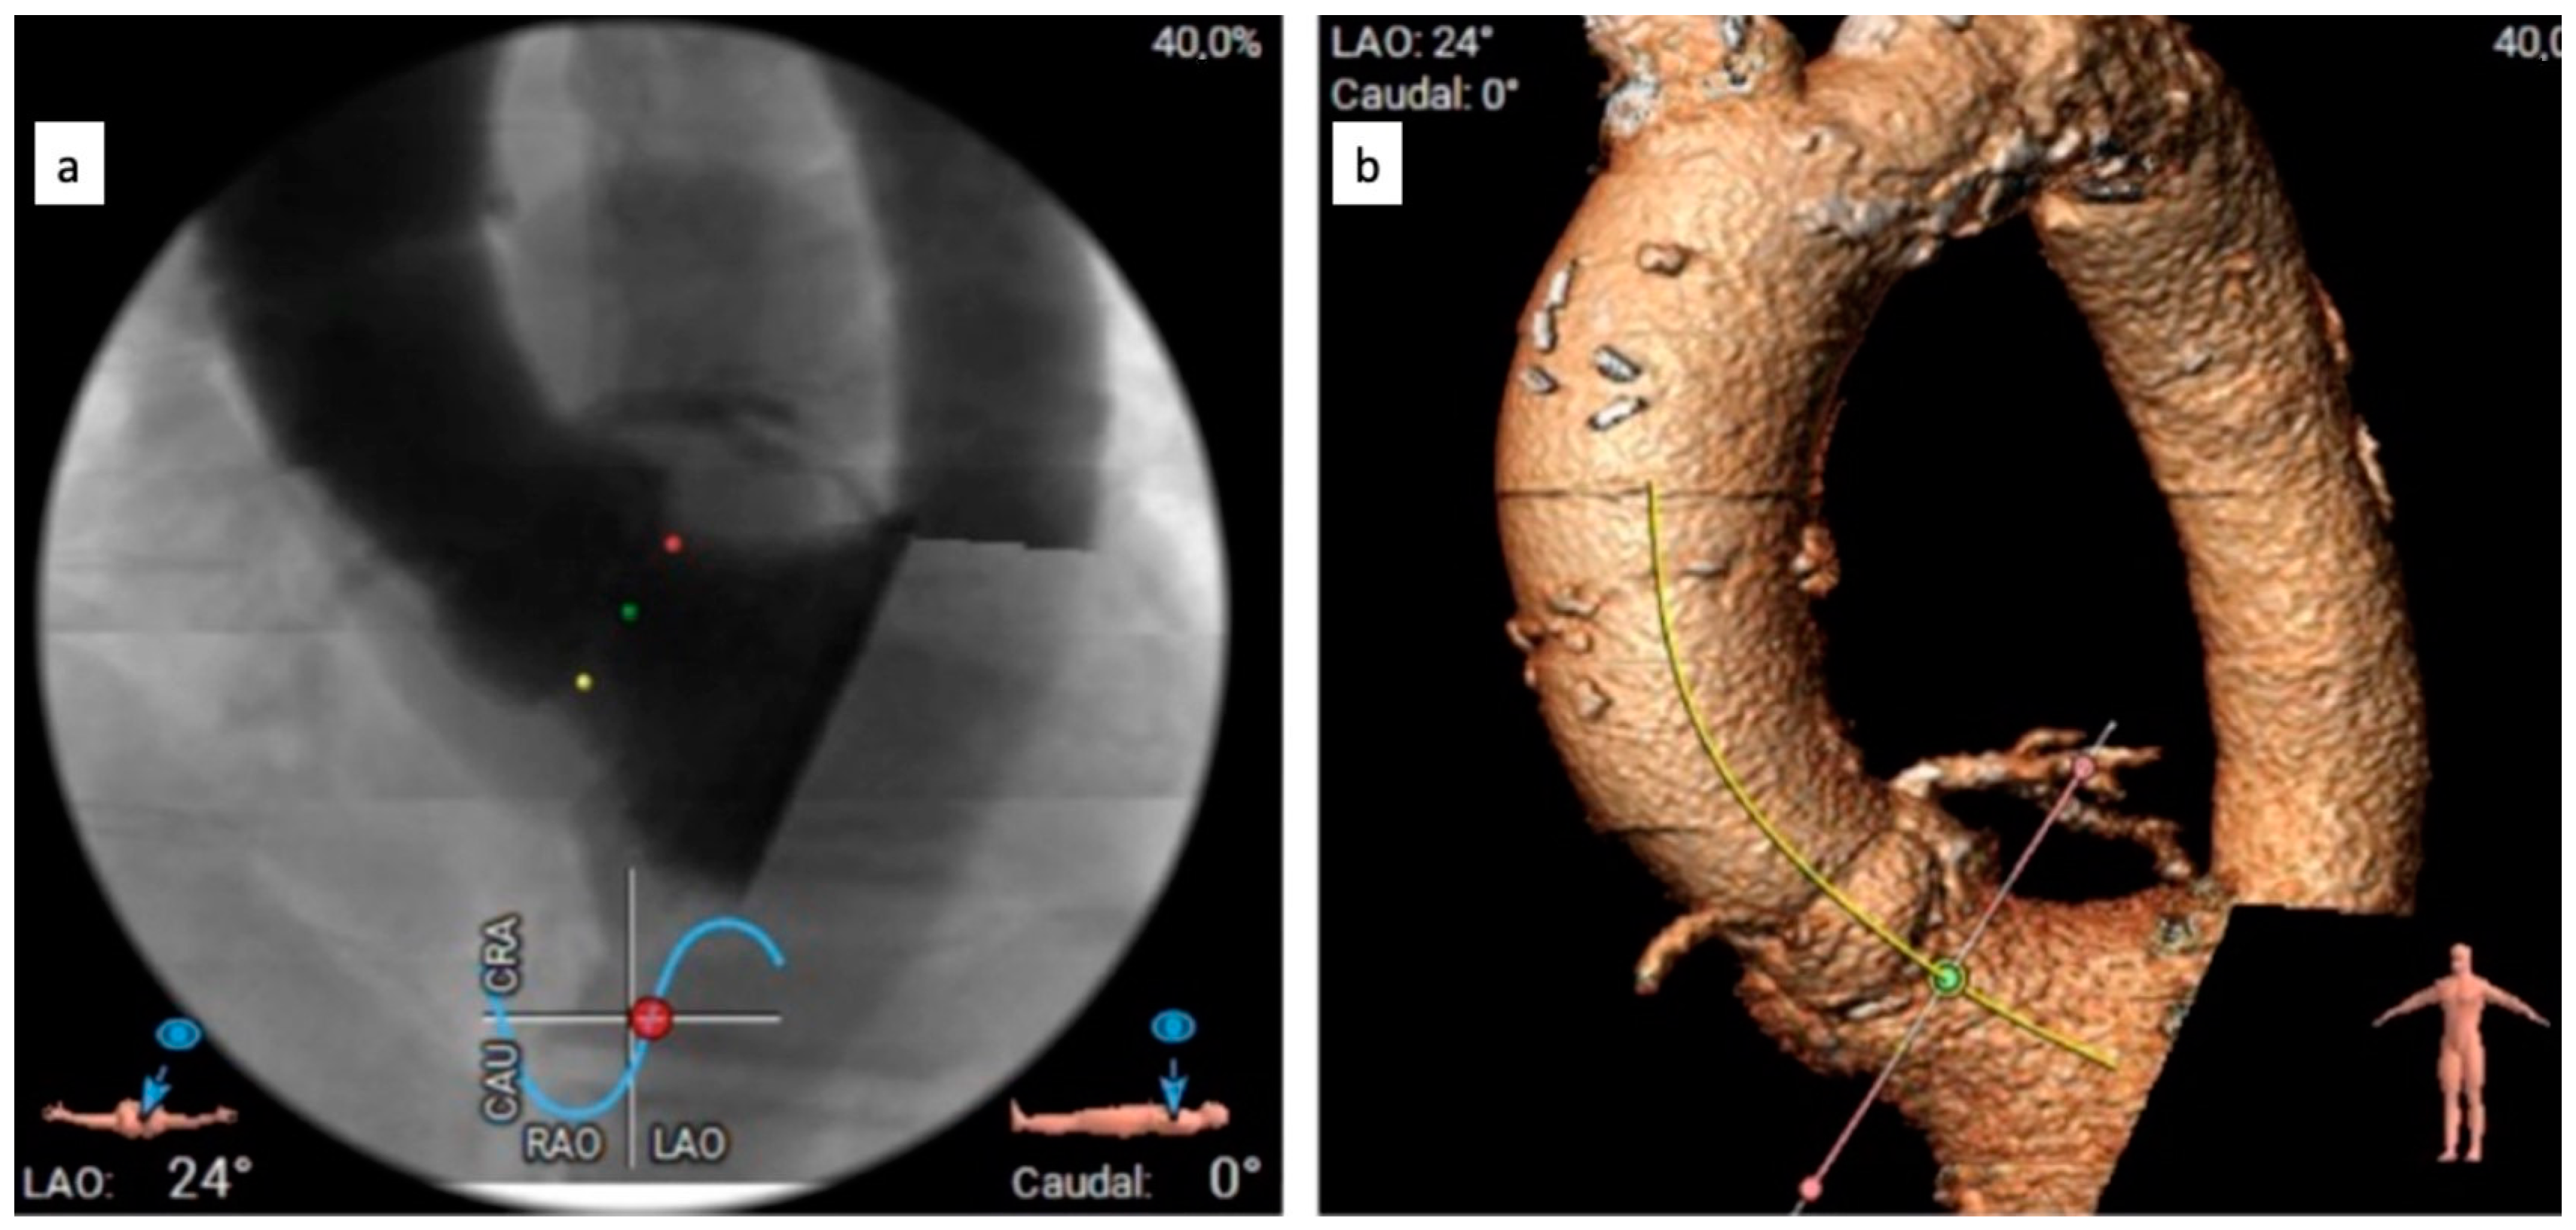

The CTA scan revealed a tricuspid aortic valve with an annulus area of 434 mm2 and dimensions near the lower limit, measuring between 26 mm and 23 mm. Notably, calcium protrusions toward the left ventricular outflow tract (LVOT) were observed below the left coronary cusp (LCC) and non-coronary cusp (NCC), increasing the risk of disturbances. To determine sizing and assess calcium behavior, a balloon valvuloplasty was considered. The left coronary artery (LCA) was found to be at a distance of 15 mm from the aortic annulus, while the right coronary artery (RCA) was at a distance of 17.5 mm. The access vessels showed calcification, with borderline diameters for eSheath placement on both sides. CTA with 3D reconstruction—access vessels is presented in Figure 1. In Figure 2 can be observed aortography of aortic root and ascending aorta, and origins of coronary arteries (a) and CTA 3D reconstruction of aortic root with coronary arteries origin, ascending aorta (b). The lines in Figure 2a represent the plane of the aortic annulus (pink) and the position perpendicular to the aortic axis (yellow). Proper alignment for prosthesis implantation

Figure 2. Investigative images: Aortography—aortic root and ascending aorta, and origins of coronary arteries (a) and CTA 3D reconstruction—aortic root with coronary arteries origin, ascending aorta (b).